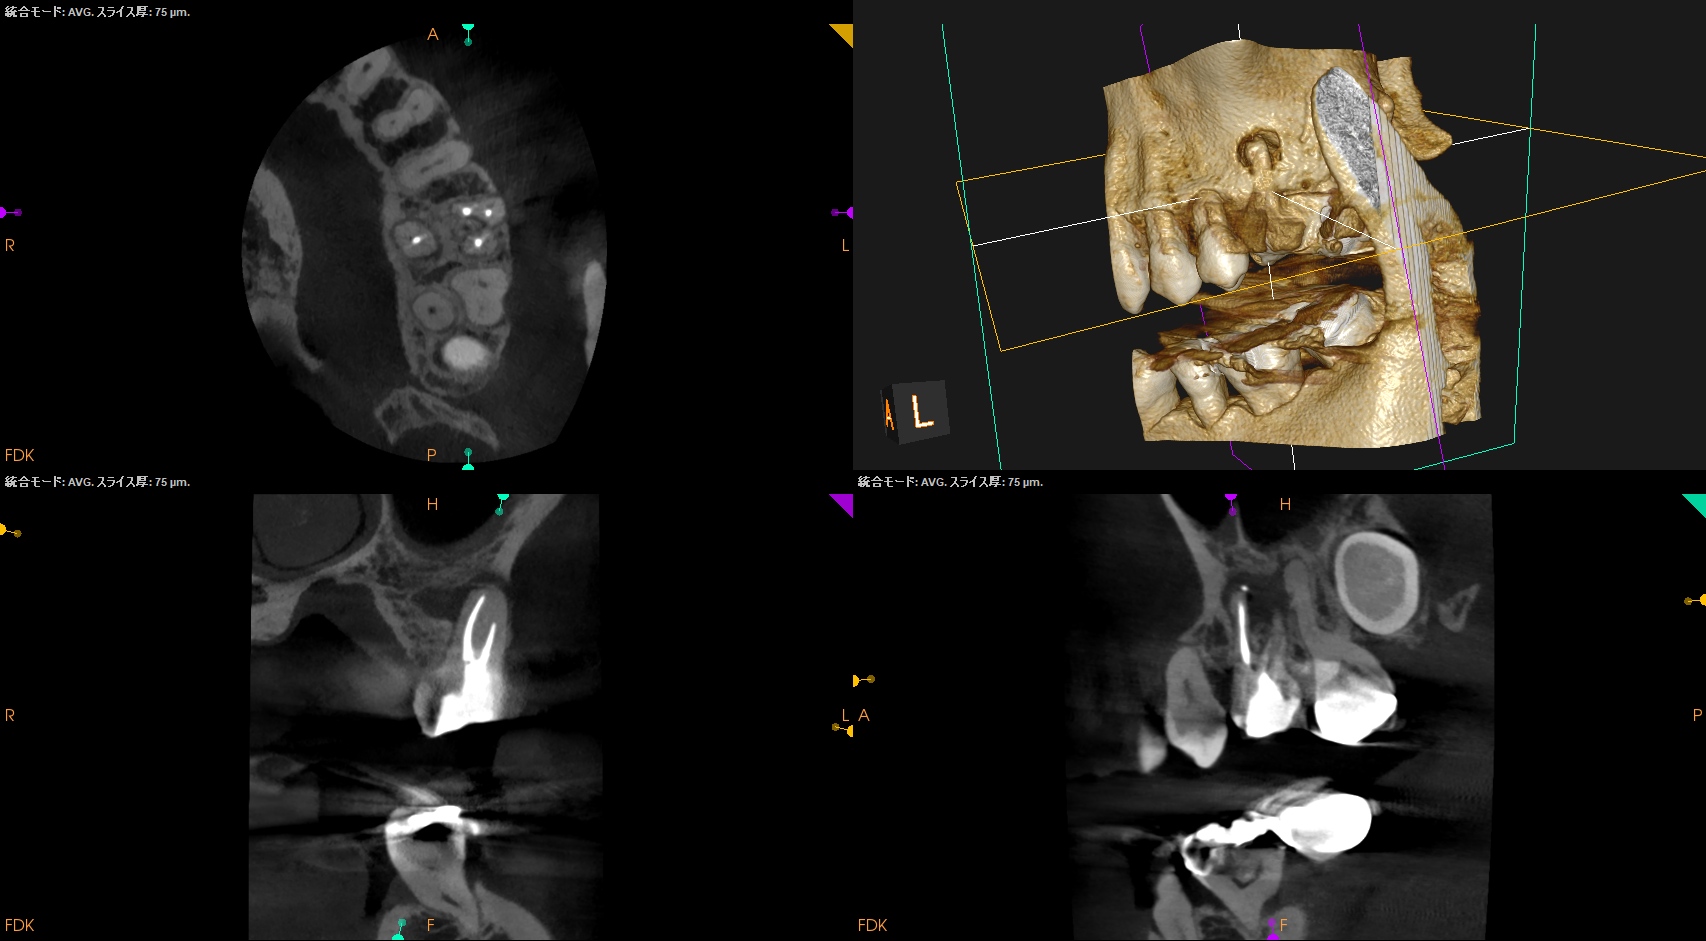

MB,DBのGutta Percha Pointを除去していった。

Poorな根管充填なので容易に除去できるはずだ。

短針・ピンセットでGutta Percha Pointを除去したならば、作業長測定である。

DBから行うが、

Gutta Percha Pointの先は石灰化しているのでMunce discovery burを使用して象牙質を除去し穿通し形成した。

次がMB1である。

が、MB1は穿通しなかった。

ということは…

MB2を見つけ穿通させないといけない事態になることがここで決定する。

その際は、

MB1よりも2.5mm口蓋近心側にMB2はあるはずだ。